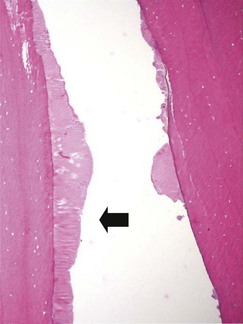

Diastemata have also been classified as closed/valve diastemata (narrower occlusally; Fig. 10.6) or open (same width at occlusal and gingival margin) diastemata (Fig. 10.7).38 Sharp overgrowths or exaggerated transverse ridges on opposite CT may widen diastemata and compress food into them;12,28 however, the most clinically significant valve diastemata have a narrow (1–3 mm) space between the teeth occlusally (Figs 10.6, 10.810.10), with no detectable overgrowth on the opposite tooth. The presence of diastemata usually leads to compression of food into the abnormal space between the two adjacent teeth, with resultant periodontal food pocketing (especially into valve diastemata) and periodontal disease,6,36 as previously illustrated in Chapter 8.

image

Fig. 10.9 A longitudinal section from an undecalcified hemimandible showing two adjacent CT (410, 411) that have a valve diastema between them. There is recession of the gingiva overlying the mandibular bone beneath the diastema, with pocket formation (arrow).

(Courtesy of Alistair Cox and Sionagh Smith.)